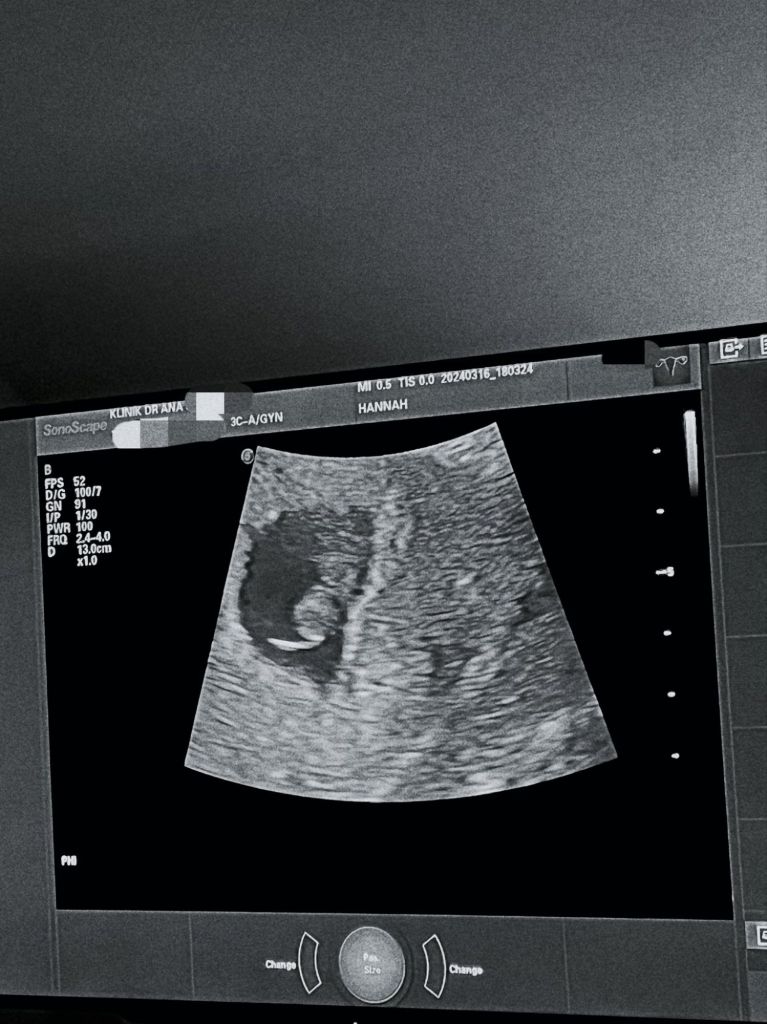

Dalam satu gambar yang penuh emosi, Hannah dilihat memegang sejambak bunga sambil berbaring di atas katil hospital, menandakan bahawa beliau sedang dalam proses pemulihan. Gambar tersebut telah menjadi simbol kekuatan dan ketabahan yang ditunjukkan oleh beliau dan suaminya dalam menghadapi situasi yang mencabar ini.